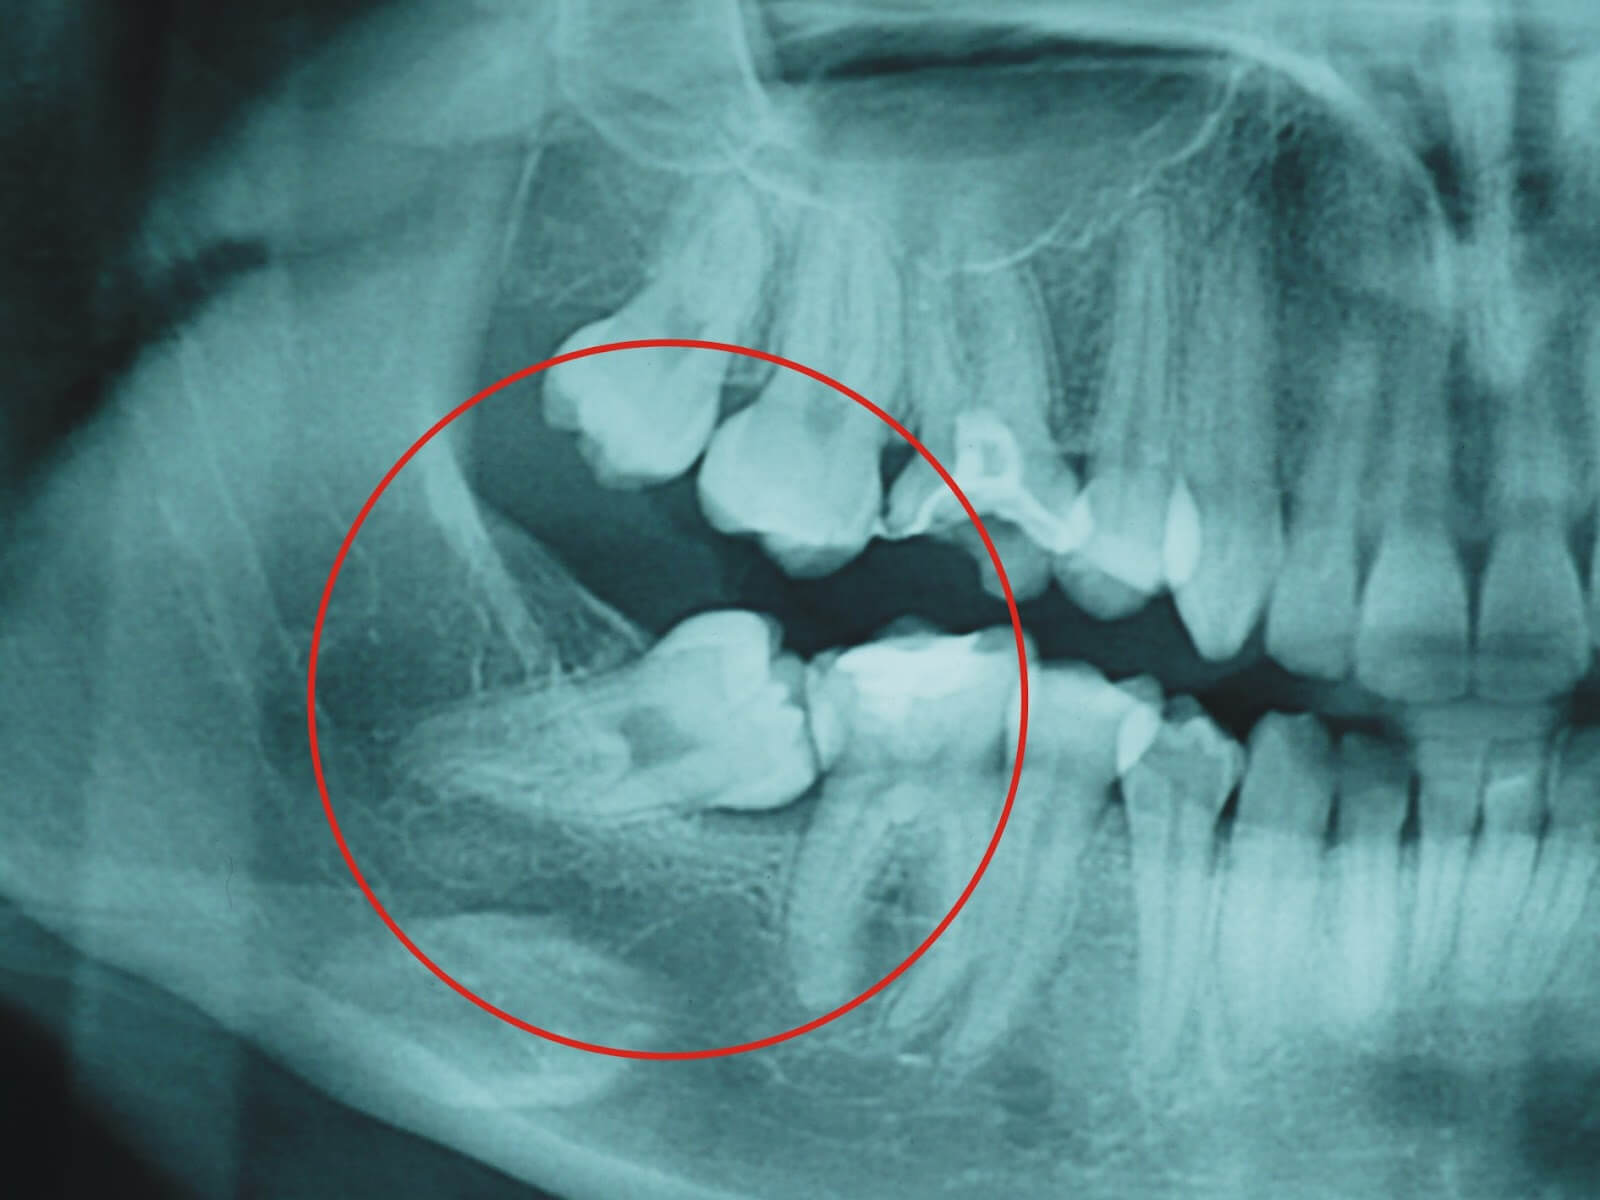

La extracción de las muelas del juicio es la intervención más frecuente en Cirugía Bucal.

Ante la presencia de un cordal (muela del juicio) podemos optar por diferentes conductas:

-Conducta